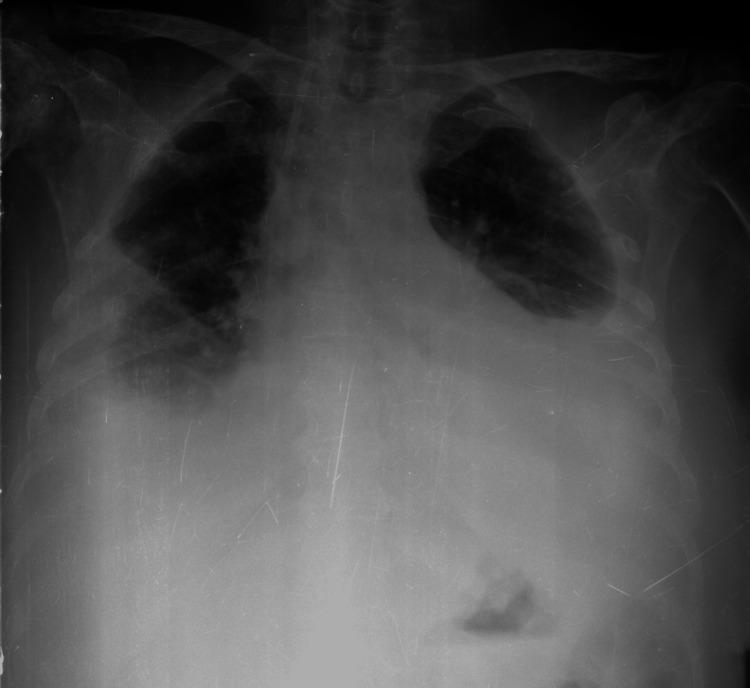

上肢深静脉血栓形成——冰山一角:病例报告及文献综述

Upper Extremity Deep Vein Thrombosis as the Tip of the Iceberg: Case Report and Review of Literature.

Unprovoked venous thromboembolism (VTE) may be the earliest manifestation of cancer. According to recent studies, approximately 5% of patients with unprovoked VTE will be diagnosed with cancer within the first year of follow-up. Although screening extensively at the time of VTE diagnosis is attractive for clinicians, current clinical guidance documents suggest only a limited cancer screening strategy. The authors describe a rare case of Krukenberg tumor of the ovary arising from a primary gastric adenocarcinoma whose first sign was an unprovoked venous thrombosis of the upper extremity.

摘要

不明原因的静脉血栓栓塞(VTE)可能是癌症的最早表现。根据最近的研究,大约5%的不明原因VTE患者在随访的第一年内将被诊断为癌症。尽管在VTE诊断时进行广泛筛查对临床医生很有吸引力,但目前的临床指南文件仅建议采用有限的癌症筛查策略。作者描述了一例罕见的卵巢库肯勃瘤,其起源于原发性胃腺癌,首发症状为上肢不明原因的静脉血栓形成。